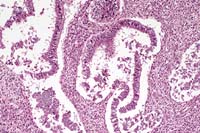

Case 20-1. Mesenteric mass. Consists of desquamated columnar epithelium.within clear spaces surrounded by a dense spindle cell stroma. 10X

AFIP Diagnosis: Mesentery (per contributor): Fibroepithelial polyp, Rhesus monkey (Macaca mulatta), primate.

Conference Note: There was considerable variation in the slides distributed with this case. Most slides contained only a single large tissue section consisting of broad papillary fronds composed of a variably dense central stroma with embedded glandular structures and a lining of cuboidal epithelial cells. Other slides contained one or two similar but smaller tissue sections in which the specimen's papillary nature was not apparent. Additional sections obtained from the contributor after the conference demonstrated histologic features clearly consistent with endometriosis.

The nature of the stroma was debated in conference; some participants interpreted it as a fibrous stroma, since in many areas its morphology was not typical of endometrial stroma when compared to archived cases of endometriosis. In humans, a diagnosis of endometriosis requires the identification of two of the three following features: endometrial glands, stroma and hemosiderin. Hemosiderin was lacking in this specimen and the stroma was not clearly endometrial.